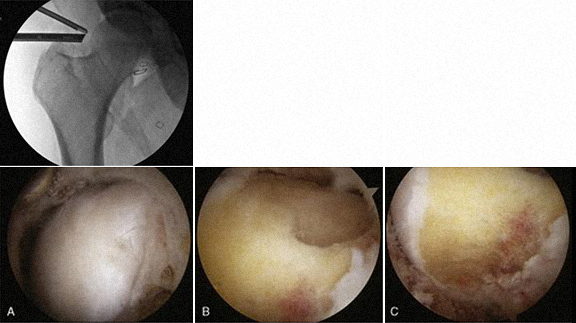

1 - Rotura do labrum 2 – Delaminação da cartilagem